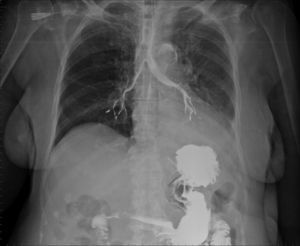

An 81-year-old woman with a history of cognitive impairment, diabetes mellitus type 2, hypertension, and cerebrovascular disease with a previous atherothrombotic ischemic stroke in the territory of the right middle cerebral artery, causing residual hemiparesis, was admitted for the study of chronic diarrhea, intestinal malabsorption, and protein-losing enteropathy. A small bowel follow-through was performed with no findings of interest, with the exception of the incidental radiological observation of contrast medium passing into the bronchial tree (Fig. 1).